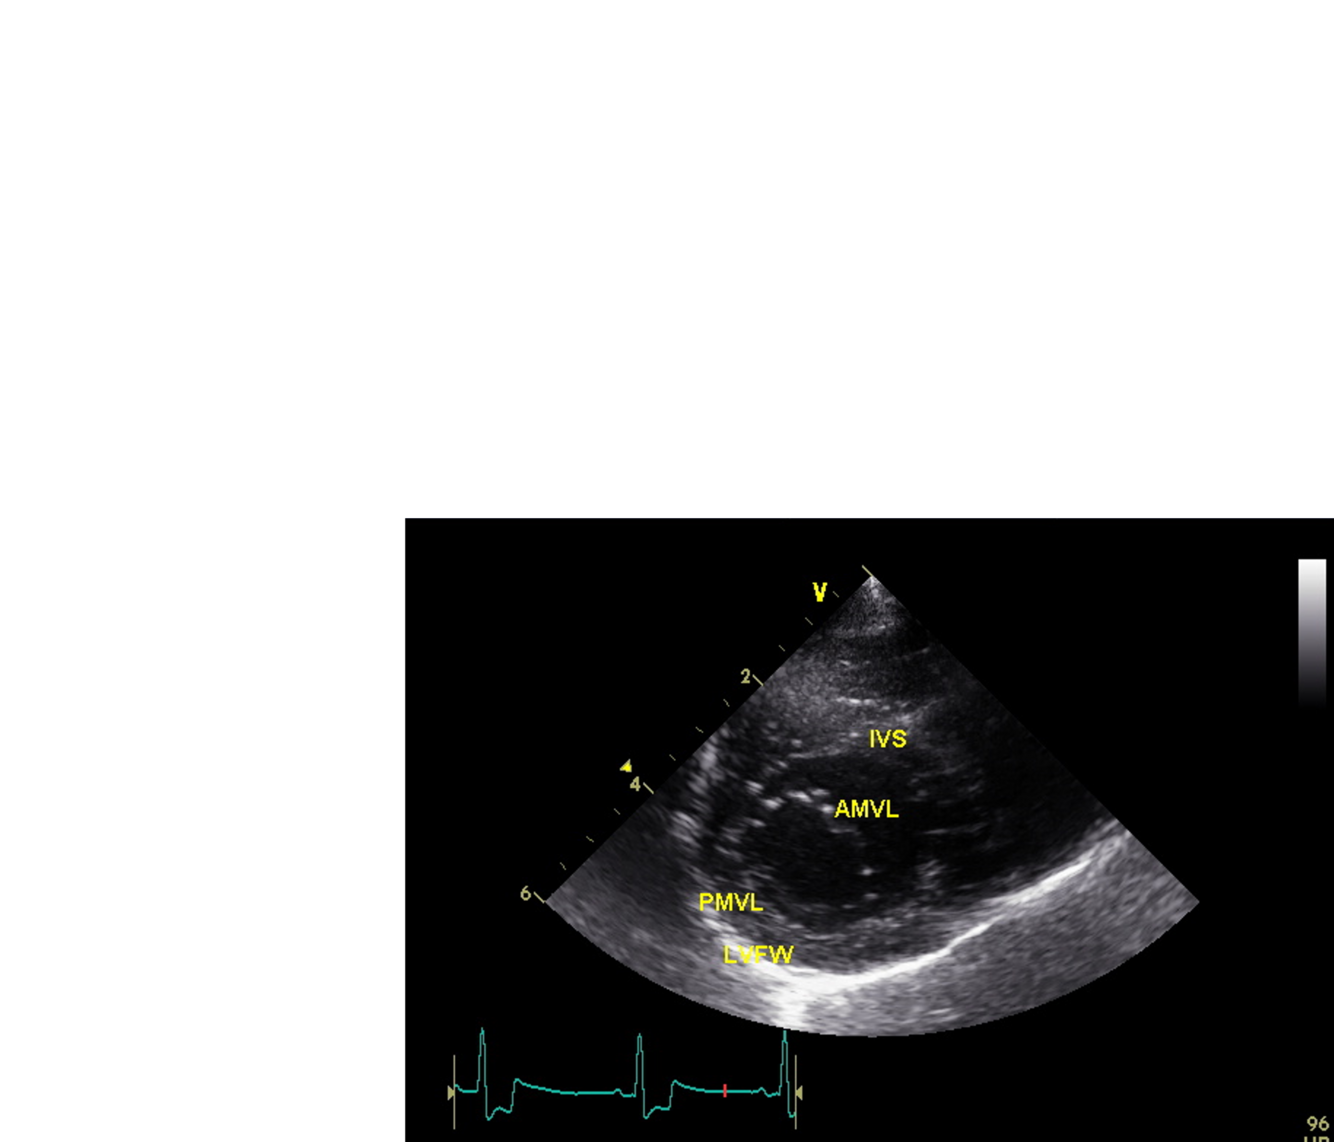

Which view is this?

A

Right parasternal long axis 4 chamber